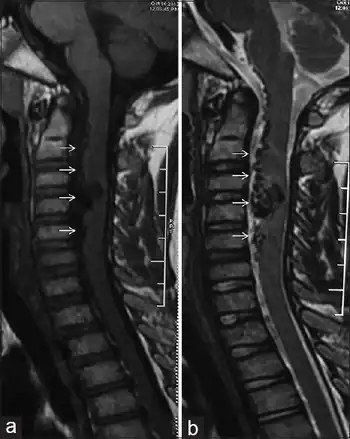

| a,b) Spinal arteriovenous malformation | |

Myelography is used to confirm the diagnosis of AVMs and it shows 'snake-like' vessels on the cord's surface. If the myelogram is positive, angiography is required to show the extent of malformation and the exact site of the shunt. Magnetic resonance imaging (MRI) may show the appropriate area. If AVMs are left untreated, 50% of patients with gradual symptoms will be unable to walk within 3 years of onset. Surgical occlusion has been shown to halt the progression and may improve any gait or incontinence.[3][6]